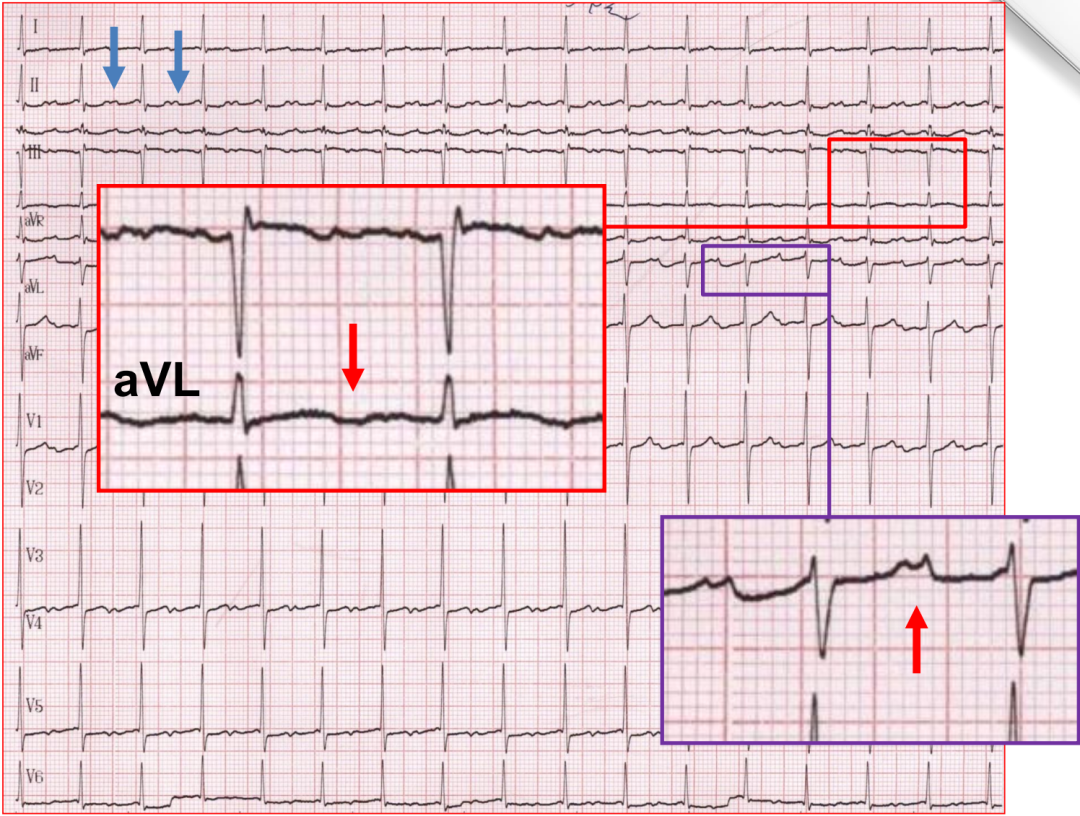

案例一

p心电图功能怎么开通异位起源P波的心电图定位_https://www.jmylbn.com_新闻资讯_第11张

p心电图功能怎么开通异位起源P波的心电图定位_https://www.jmylbn.com_新闻资讯_第12张